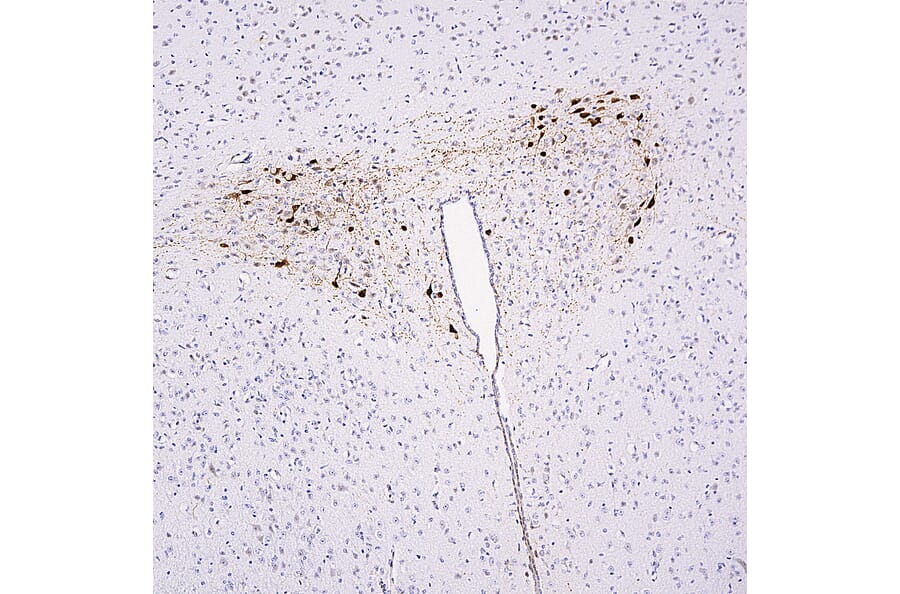

The endosomal Commander assembly associates with the sorting nexin-17 (SNX17) cargo adaptor to regulate cell surface recycling of internalised integral proteins including integrins and lipoprotein receptors. Here, we identify leucine rich melanocyte differentiation associated (LRMDA) as a Commander binding protein. We reveal that LRMDA and SNX17 share a common mechanism of Commander association, and that LRMDA simultaneously associates with Commander and active RAB32, establishing distinct RAB32-LRMDA-Commander and SNX17-Commander assemblies. Functional analysis in melanocytes reveals distinct roles for RAB32-LRMDA-Commander and SNX17-Commander in melanosome biogenesis. We reveal how LRMDA mutations, causative for oculocutaneous albinism type 7, a hypopigmentation disorder accompanied by poor visual acuity, uncouple RAB32 and Commander binding thereby establishing the mechanistic basis of this disease. Our discovery of this alternative Commander assembly highlights the plasticity of Commander function in human pigmentation and extends the Commander function beyond the SNX17-mediated regulation of cell surface proteome.

Commander is an endosome associated sixteen protein assembly that associates with the sorting nexin 17 (SNX17) cargo adaptor to regulate cell surface recycling of internalised integral membrane proteins including integrins and lipoprotein receptors. Mutations in Commander are causative for Ritscher-Schinzel syndrome (RSS), a multiorgan developmental disease associated with a core triad of cerebellar-cardiac-craniofacial malformation. Here, using unbiased proteomics and computational modelling, we identify leucine rich melanocyte differentiation associated (LRMDA) as a novel Commander binding protein. Using recombinant protein reconstitution, we show that LRMDA simultaneously associates with Commander and active RAB32, and, by revealing that LRMDA and SNX17 share a common mechanism of Commander association, establish the mutually exclusive nature of RAB32-LRMDA-Commander and SNX17-Commander assemblies. From functional analysis in human melanocytes, we establish an essential role for RAB32-LRMDA-Commander in melanosome biogenesis and pigmentation and reveal a distinct functional role for SNX17-Commander in this organelle biogenesis pathway. We reveal how LRMDA mutations, causative for oculocutaneous albinism type 7 (OCA7), a hypopigmentation disorder accompanied by poor visual acuity, uncouple RAB32 and Commander binding thereby establishing the mechanistic basis of this disease. Our discovery and characterisation of this alternative Commander assembly establishes an unrecognised plasticity of Commander function within a highly complex organelle biogenesis pathway. This extends Commander function beyond the confines of SNX17-mediated cell surface recycling into RAB32-family mediated biogenesis of lysosome-related organelles and, potentially, other RAB32 regulated pathways including host-pathogen defence mechanisms. Our work also extends the breath of Commander pathway dysfunction for human disease.